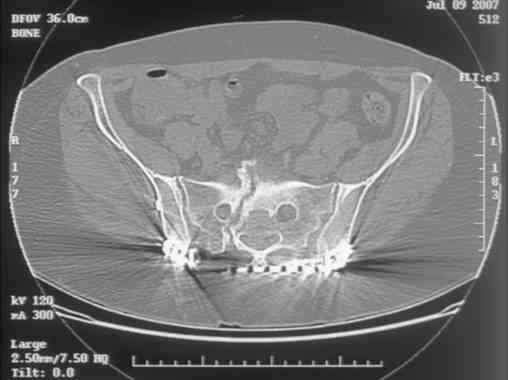

I can't see the axial CT images well enough to detail the potential sacral issues....can you magnify them?

Here is a magnified view. Sorry about the quality but the CT was scanned into our system.

Thank you...it might help to remove the disengaged and other iliosacral screws then insert longer lag screws into the upper sacral segment and if anatomically feasible into the second sacral segment as well.